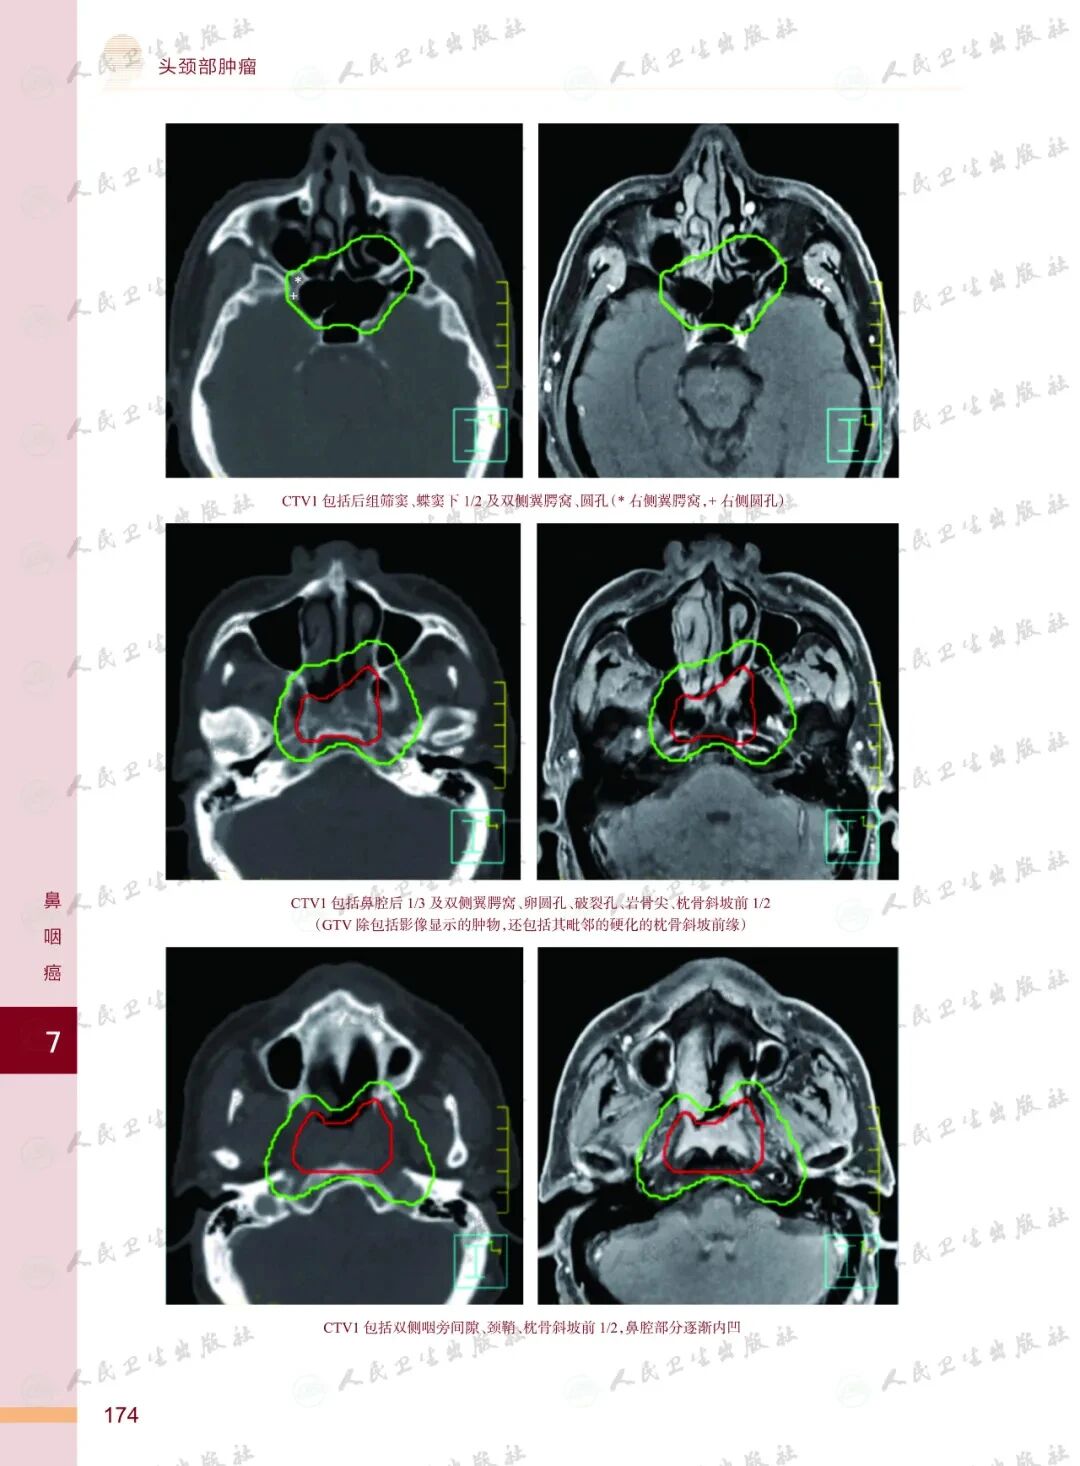

《头颈部肿瘤放射治疗图谱》

——不止是图谱,更是随唤随应的临床良师